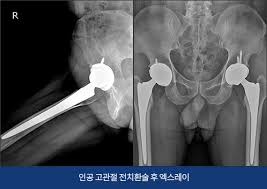

- 진단적 검사: 의사가 필요할 경우 정기적으로 X-ray나 MRI를 통해 관절의 상태를 체크할 수 있습니다.

- 인공관절 치환술: 가장 일반적인 고관절 수술입니다. 퇴행성 관절염이나 심한 외상으로 인해 고관절이 손상된 경우, 인공 관절로 대체합니다. 이 수술은 대개 1-2시간 가량 소요되며, 회복이 길어질 수 있습니다.